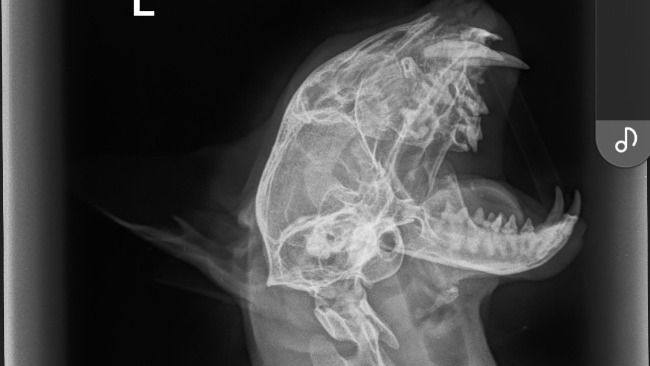

Wykonaliśmy również RTG w 4 projekcjach. Na pierwszy rzut oka wszystko wygląda dobrze, ale czekamy jeszcze na dokładny opis od specjalisty. Dodatkowo kupiłam Kokosowi leki odrobaczające na 3 miesiące, ponieważ jedną z możliwych przyczyn problemów mogą być pasożyty w płucach.

Poniżej dołączam zdjęcia RTG oraz potwierdzenia płatności.

Dostaliśmy opis od specjalisty. Kokos ma powiększone obie zastawki serca oraz wyciek w zatokach ( stąd ten świst u niego ). Będziemy podawać mu antybiotyk w zastrzykach i konieczna jest wizyta u kardiologa (ma odbyć się w przyszły wtorek) . Niestety to wszystko generuję kolejne koszty plus leki na serce które zapewne dostanie po wizycie u kardiologa. Z tego względu wciąż proszę o wpłaty i z całego serca dziękuję!